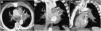

Axial fused PET/CT image (A) demonstrates a hypermetabolic mass (asterisk). Axial CT image (mediastinal window) from the CT portion of the PET/CT (B) study shows an increase in the size of the left hilar mass (asterisk) and a greater secondary encasement of the left internal mammary artery graft (arrow) with respect to the previous imaging study. Coronal CT image (mediastinal window) from the CT portion of the PET/CT (C) better depicts the encasement of the coronary artery bypass graft (arrows) by the mass (asterisk).

A 70-year-old ex-smoker man (45 pack-year history of smoking; quit smoking 4 years earlier) presented to our hospital with a new-onset symptomatic AF. His past medical history was significant for coronary artery disease (treated with CABG four years earlier), mitral valve disease (treated with mitral valve replacement at the same time of the CABG), hyperlipidemia, and chronic obstructive pulmonary disease. Since the AF episodes became persistent in spite of medical treatment, a cavotricuspid isthmus (CTI) ablation was planned. The CTI ablation procedure was successful for controlling the patient's AF. A chest radiograph performed at that time showed a subtle left parahilar opacity that was presumed to be of infectious origin (Fig. 1); however, given the absence of thoracic symptoms, a thoracic computed tomography (CT) was recommended. A chest CT was performed 2 weeks later and showed a left hilar mass invading the mediastinum and the left internal mammary artery (LIMA) graft to the left anterior descending coronary artery, consistent with a lung cancer (Fig. 1). The patient denied any chest pain, hemoptysis or coughing in the previous weeks, and an electrocardiogram (ECG) performed at that time (post-CTI) did not show any abnormalities. A bronchoscopic biopsy confirmed a large cell undifferentiated lung carcinoma. A contrast-enhanced whole-body positron emission tomography (PET)/CT detected small liver and adrenal metastases, consistent with a stage IV lung cancer. The patient was started on systemic chemotherapy, but unfortunately the cancer did not respond to treatment. A follow-up PET/CT performed 3 months later showed an increase in the size of the lung mass, a decrease in the diameter of the LIMA graft secondary to an encasement by the surrounding tumor (Fig. 2). Shortly after this follow-up study, the patient presented to the Emergency Department with tachycardia, chest pain, a new ST elevation on ECG in the precordial and lateral leads, and elevation of cardiac troponin levels, consistent with an extensive myocardial infarction. The patient was admitted to the oncology unit and died from cardiac arrest 24h later.